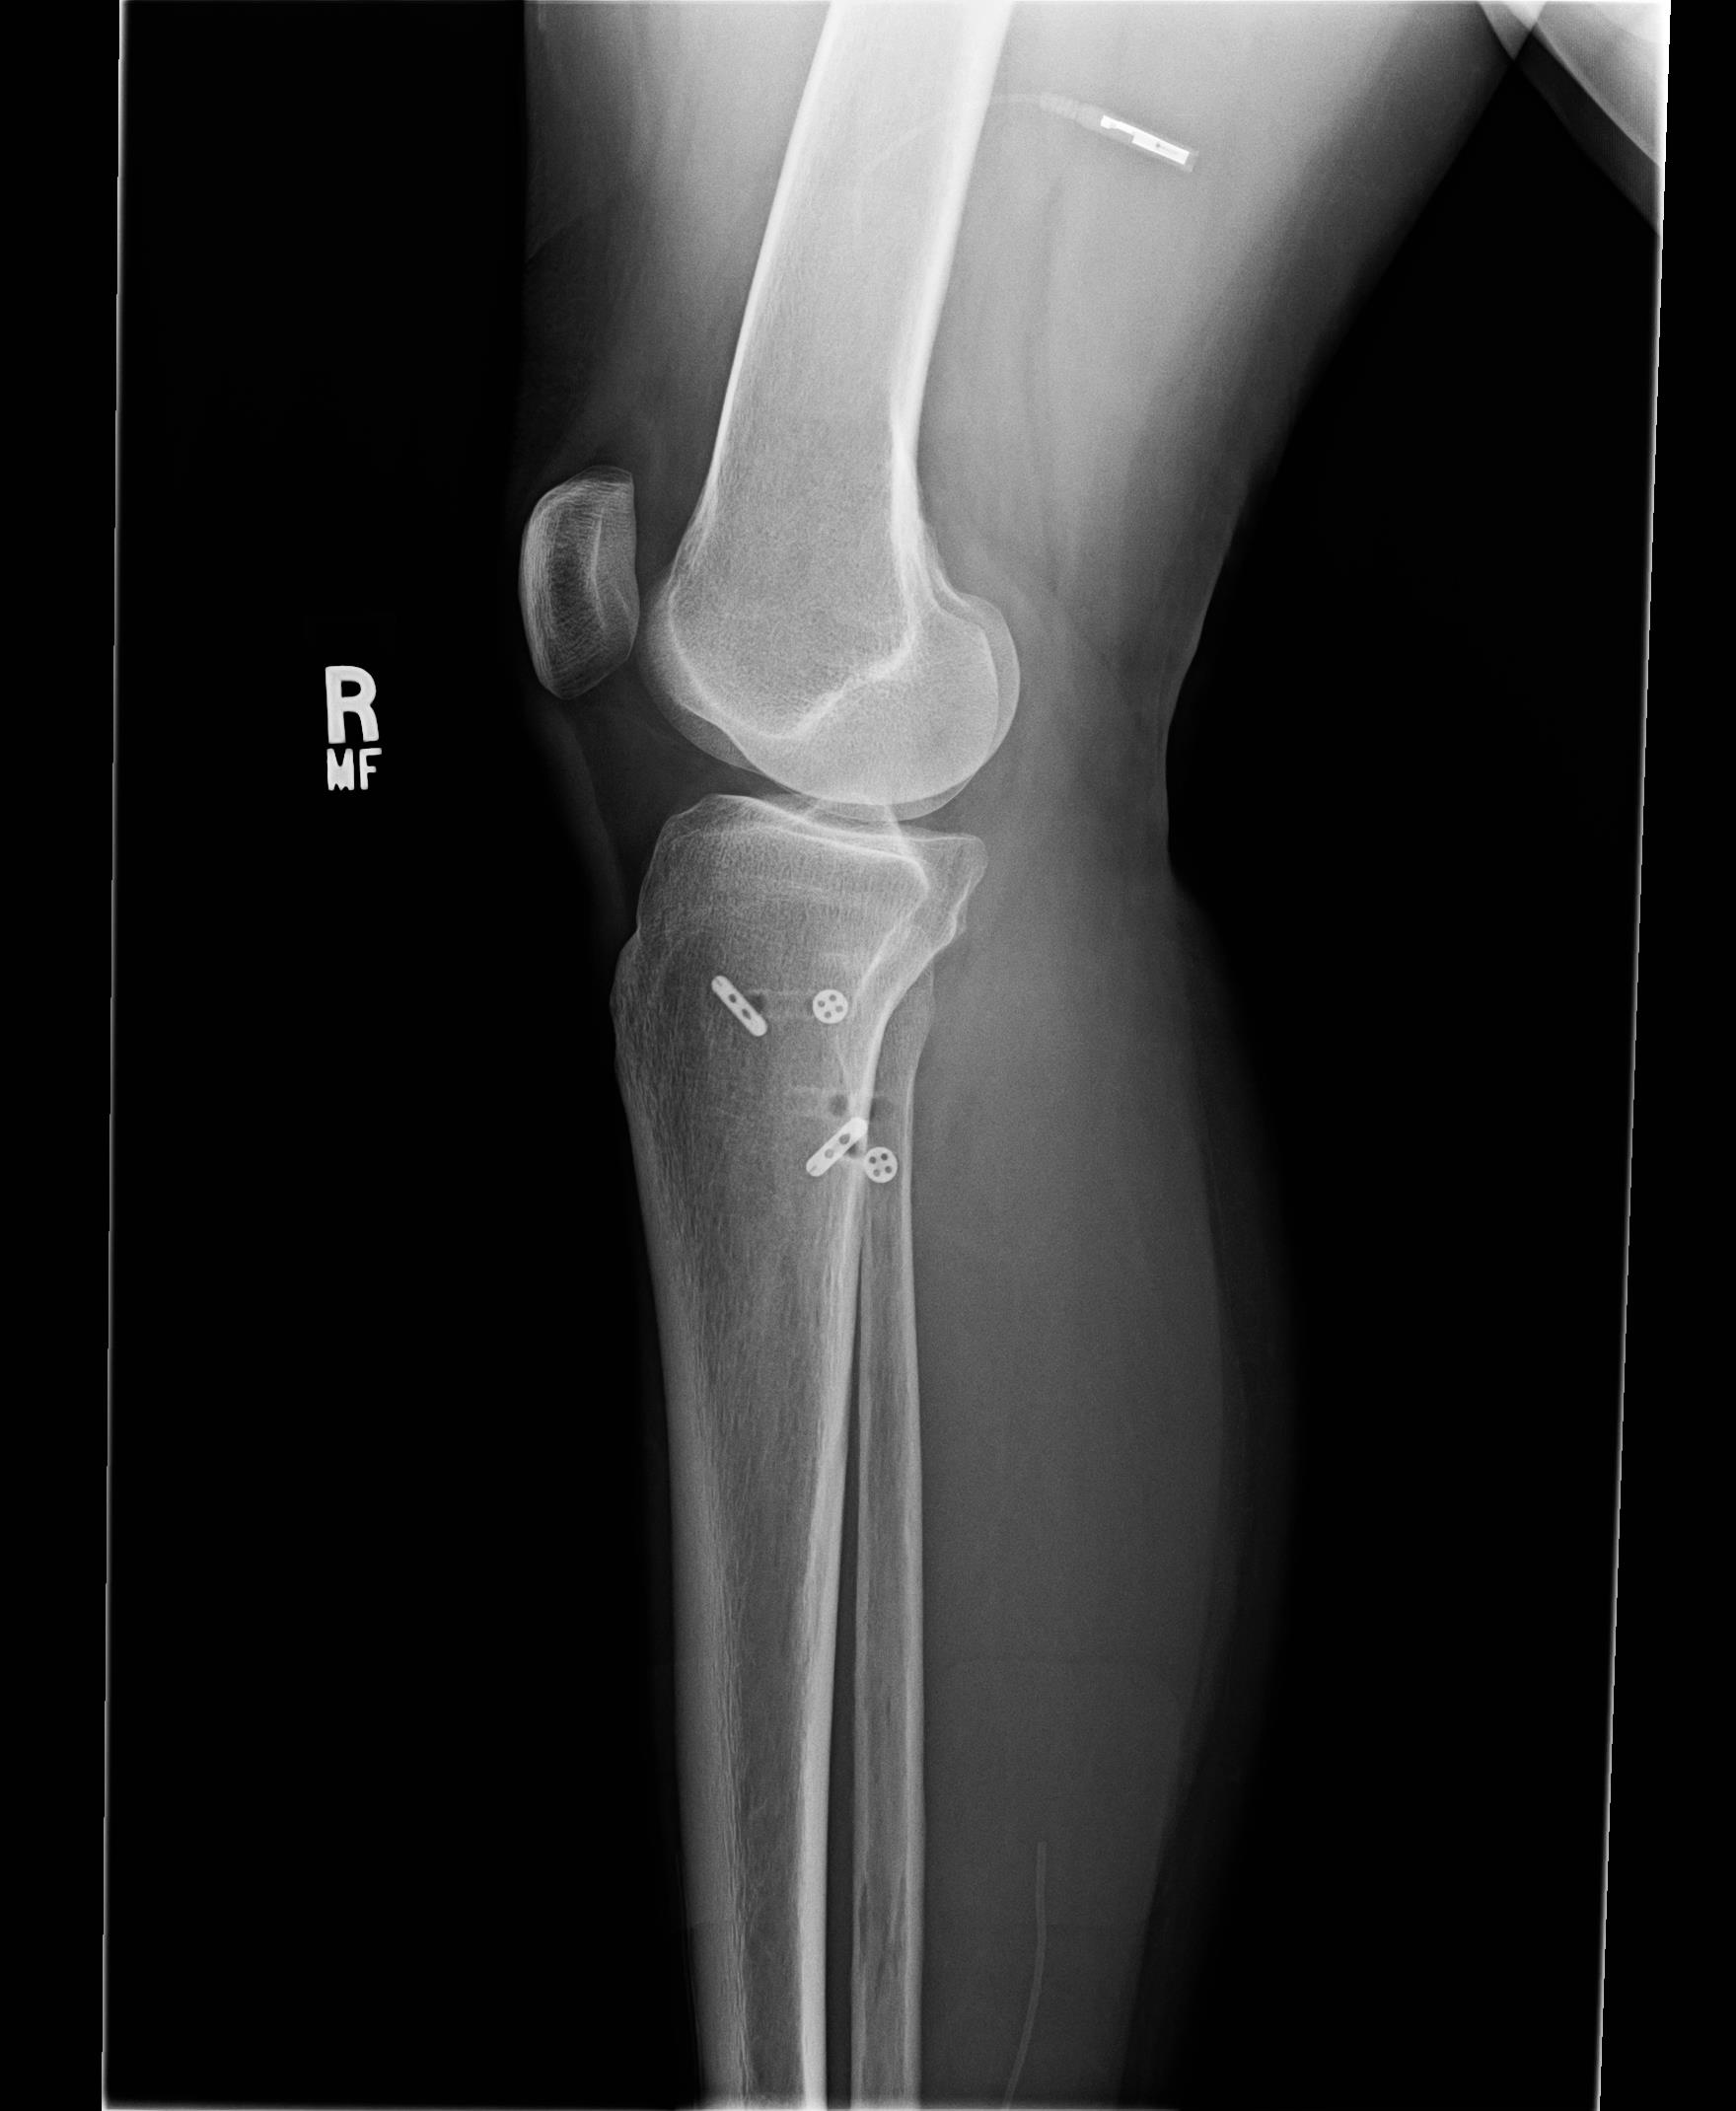

Post surgical X-rays are shown farther down in this blog. For those readers that want the surgical procedure details, please click each link for the PDF pages of the surgical report:

2. Dr. Main and I had discussed my right ankle joint still having some slight pronation and pain around the distal tib-fib. During surgery after doing the proximal fixations and tightening of the proximal syndesmosis, he checked the distal syndesmosis and it still showed some slight instability. He therefore went ahead and placed another Arthrex TightRope Fixation into the distal tib-fib of the ankle. All the fixations can be seen in the X-rays below in this blog.

Monday, 3-31-14— First Follow up appointment at 4 days since surgery. Post surgical x-rays taken of my right lower leg and ankle at Dr. Main’s office (click on photos to enlarge):